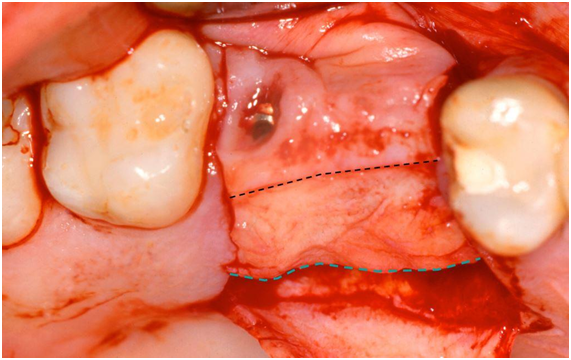

A 45-year-old female patient, after having undergone the installation of dental implants of the external hexagon type in the region of the right upper second premolar and first molar (Figure 1), presented the complaint of depression in the region of the implants, causing an aesthetic defect, visible when smiling (Figure 2). In the anamnesis, no relevant aspects were observed in the patient's previous and current medical history that could interfere in the diagnosis, treatment and prognosis of the intervention to be performed. The correction of the defect was performed after four months of the implants installation, using the technique of mucogingival surgery, in order to gain soft tissue in thickness. Prior to the surgical procedure, the patient received control of biofilm and orientation for maintenance of periodontal health. Then, a subepithelial connective tissue graft (SCTG) was performed using the roller technique. Local infiltrative anesthesia was performed by vestibular and palatine of the defect region using mepivacaine anesthetic 2% with vasoconstrictor. An incision was made with a 15C scalpel blade on the bony crest, further shifted to the palatine, and the dissection plane was crown-apical. Two other slightly divergent incisions were made in the palatal region to divide the epithelial flap. After splitting the flap, an incision at the base of the connective tissue attached to the periosteum was performed (Figure 3) to release the graft, which was moved to the receiving area (vestibular mucosa). The graft was folded under the vestibular flap (Figure 4) and stabilized with isolated suture at the base of the flap. Healing abutments were installed. The vestibular flap was repositioned around the abutments with the graft stabilized by the suture, also performed on the sides and at the base of the wound with interrupted stitches of resorbable Vicryl 5.0 (Figure 5). Compressive suture was performed on the palate over hemostatic sponge of hydrolyzed collagen (Figure 6). The postoperative period consisted of orientations to the patient regarding hygienic care, feeding, rest and prescription of analgesic (paracetamol 750 mg) and anti-inflammatory (nimesulide 100mg). Chemical control of bacterial plaque was also prescribed by means of two 1-minute daily mouthwashes at twelve-hour intervals with 0.12% chlorhexidine digluconate. Patient returned to the postoperative period after seven days, and the suture was removed after 14 days. Patient was kept under control for 30 days, and she was referred for prosthetic rehabilitation after 4 months of surgery. With two months of proservation, tissue gain was observed in thickness (Figure 7). For gingival tissue conditioning, a provisional prosthesis was installed after three months of the mucogingival surgery (Figure 8). It was observed that, after the 6-month period of proservation, the tissue gain in thickness by the SCTG favored the vestibular emergency profile of the prosthesis and the new conformation of the gingival papillae (Figure 9) (Figure 10) (Figure 11).

Figure 3 The black dashed line signals the first incision dividing the epithelial flap and the dashed line in blue signals the incision of the release of the conjunctive graft already displaced from its apical portion.